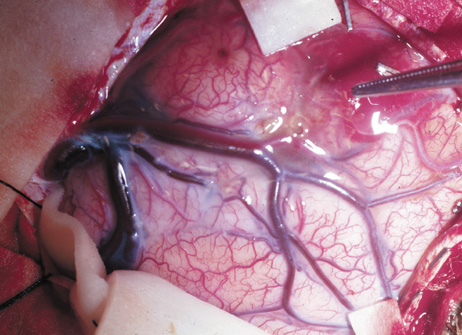

Optic nerve gliomas may involve the optic chiasm and be associated with endocrine disorders or nystagmus.68–70 Surgical excision of chiasmal gliomas (Fig. 6) carries a high risk of visual loss. Invasion of the hypothalamus or the third ventricle carries a poor prognosis, with greater than 50% 15-year mortality rate.71 One review of radiation treatment for chiasmal gliomas collated data from small case series and found no significant long-term improvement in visual function, progression, or mortality with radiation treatment.71 Other reports suggest that radiation doses over 4500cGy improve symptoms and slow progression of chiasmal gliomas over several years.72 Adequate tumor coverage by radiotherapy results in irradiation of normal brain and nearly all children need hormone replacement.73 Chemotherapy is an alternative.74,75